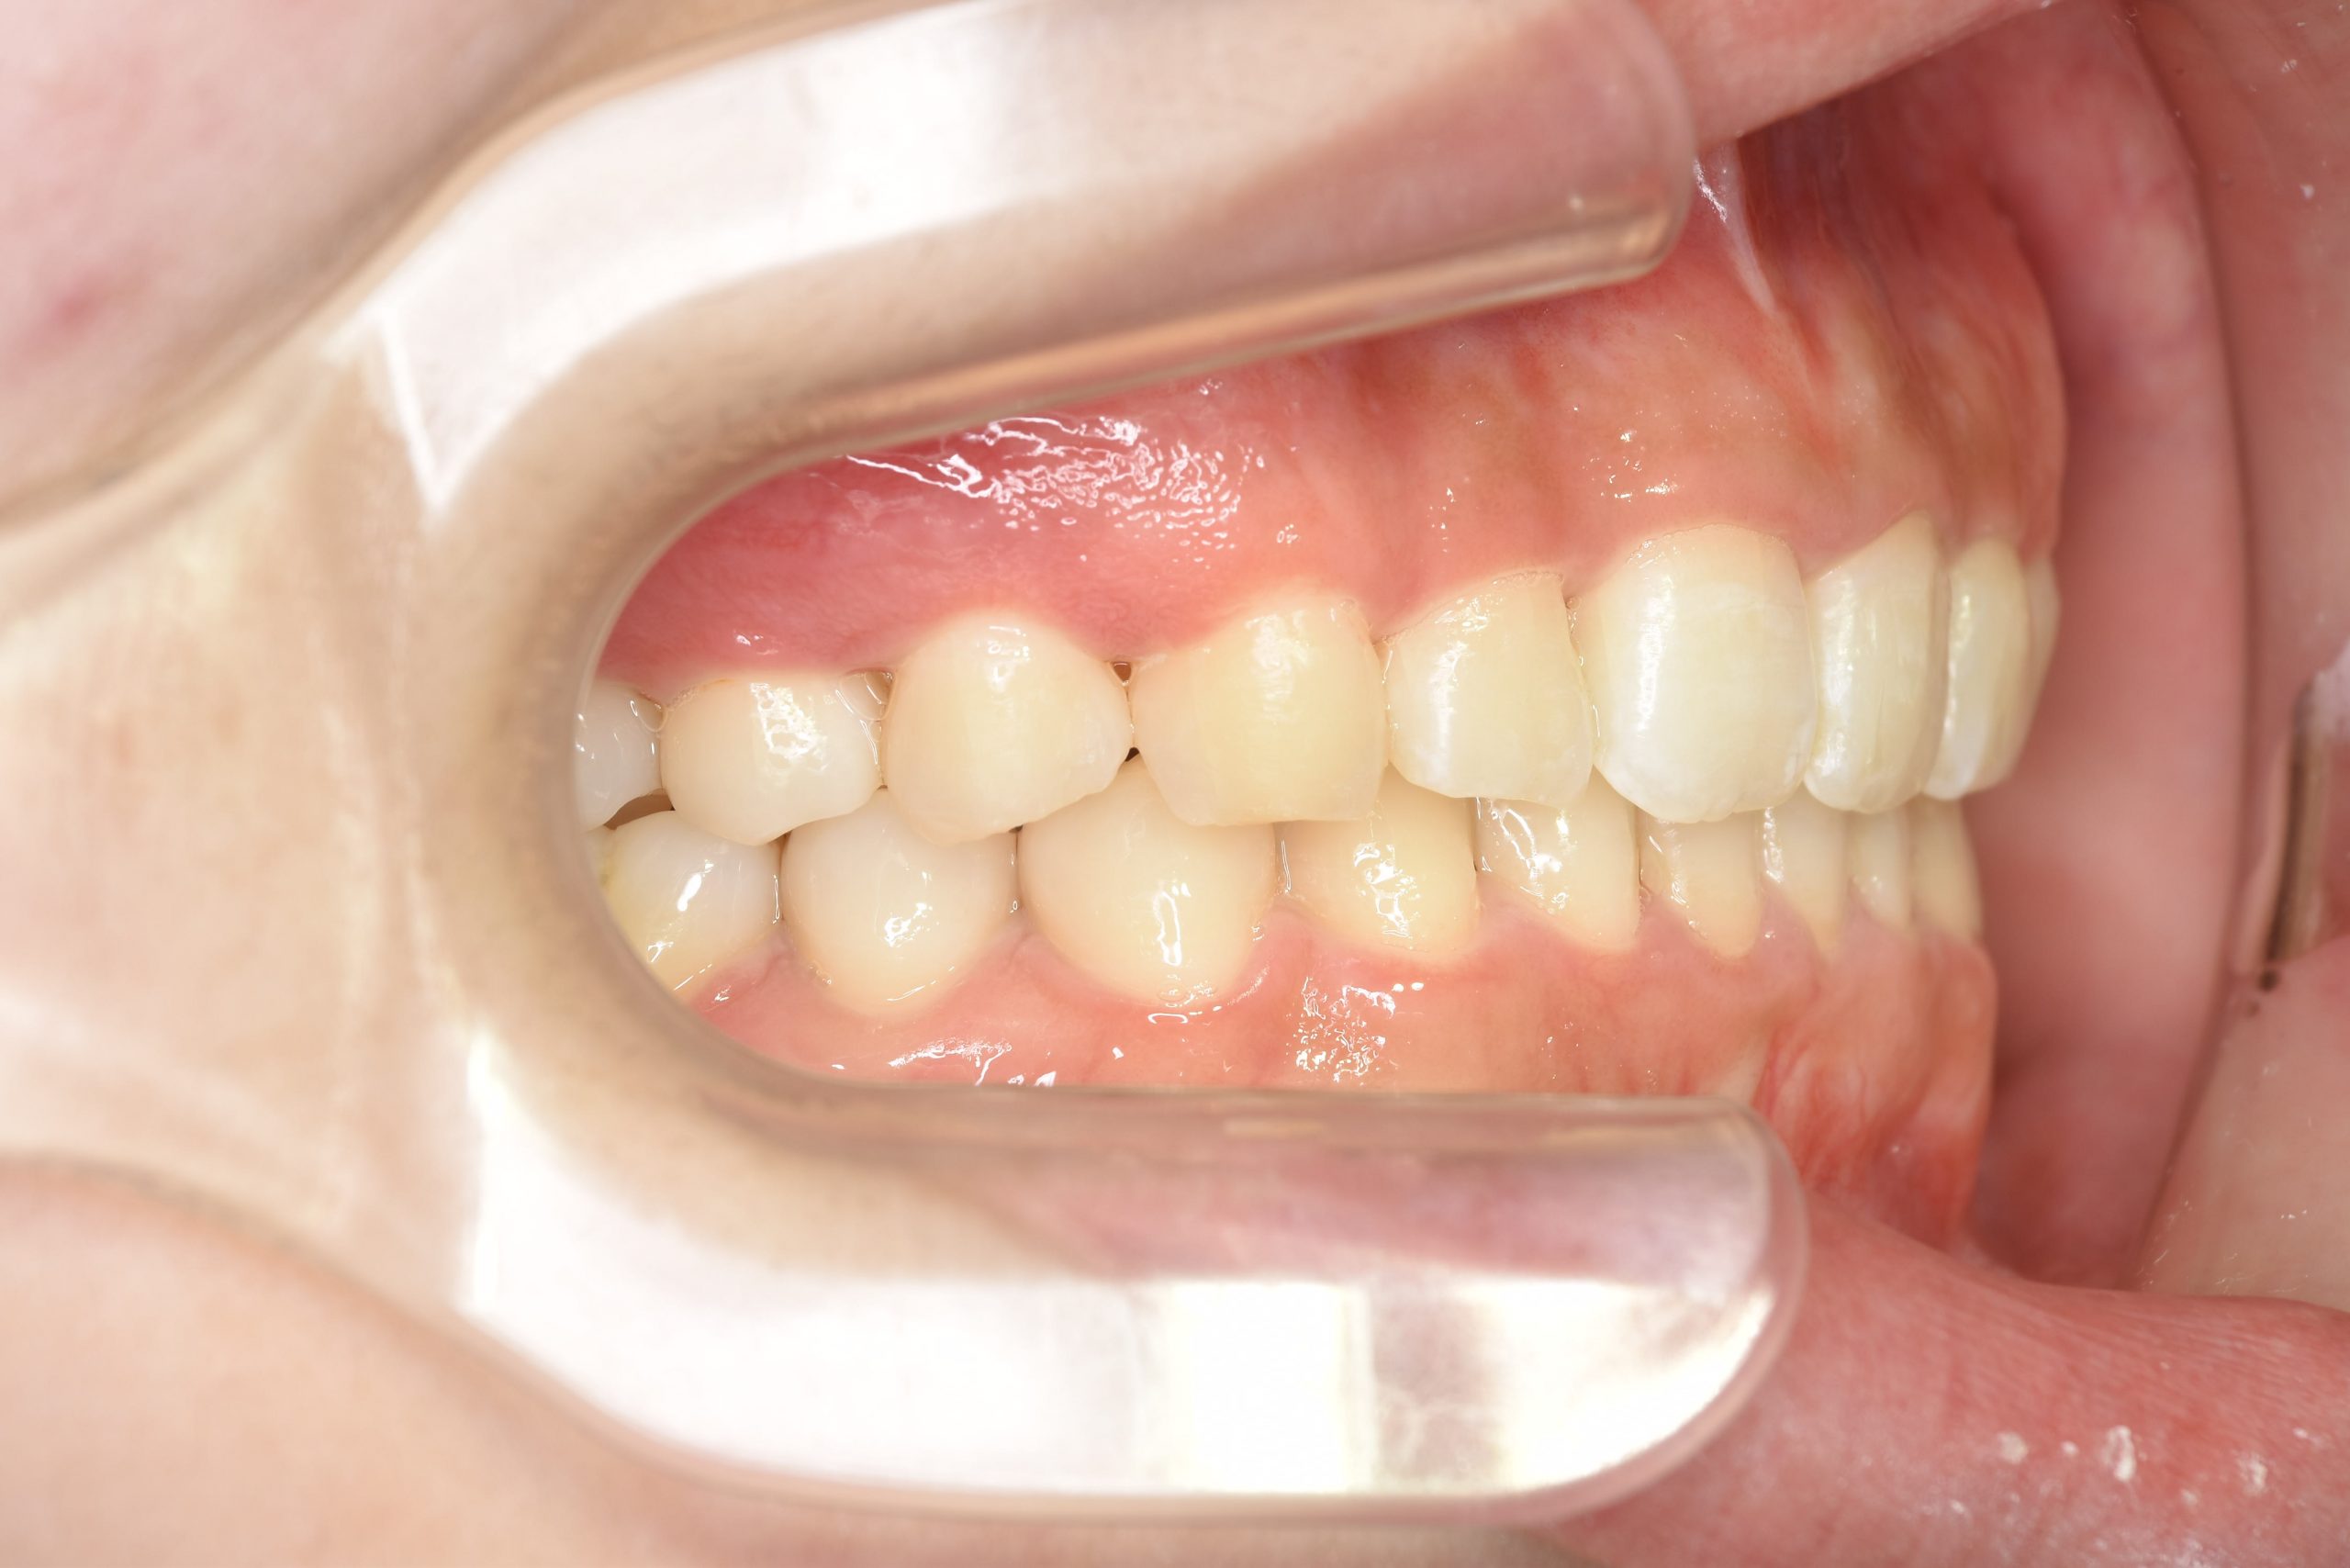

アフター

インビザライン矯正治療|症例_315

主訴 食べ物を前歯で噛み切れない|上顎の右側の歯が重なっている|下の歯がガタガタ

施術内容 MSEと下顎リンガルアーチを用いて上下顎骨を拡大した。

その後アライナー型矯正装置(インビザライン)を用いて非抜歯で歯牙を配列した。

口元の突出感、鼻閉症状、鼾は改善された。

治癒期間 1年6ヶ月間